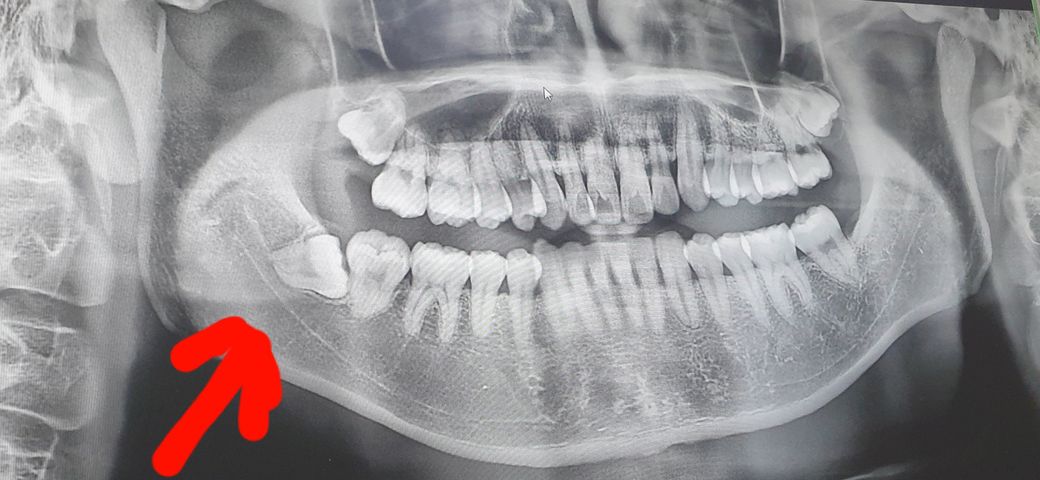

병원에서 몰래? 찍은 엑스레이 사진이에요

제 증상은 지속적인 통증은 아니고 격하게 움직이거나 하품 등 턱을 크게 움직일때 오른쪽 어금니에 압통?이 느껴집니다

큰 통증은 아니고 사소한 통증입니다만 거슬리는건 어쩔 수 없네요

제가 간 치과의원에서는 현재 사랑니가 아랫턱 신경선과 맞닿아 있어 위험하므로 대학병원급은 가야 뺄수 있다고 하더라고요

사랑니의 경우 옆으로 누워서 나고있으며 앞치아에 만나있기 때문에 시간이 지난다고 치아위치가 바뀌거나 할 가능성은 거의 없습니다.

현재 사진과 같은 사랑니는 시간이 지난다고 해서 위치가 바뀌거나 더 나오거나 하진 않을 것으로 보입니다.

사랑니가 저 위치에서 이동하지는 않을겁니다. 사진상으로 보면 신경과 맞닿아 잇어보이긴합니다. 안아프실때 대학병원에 약속을 미리 잡아놓고 발치를 하시는게 좋을것같습니다

사랑니가 옆으로 누어있는 수평매복 사랑니 입니다.

파노라마 상에서 봤을때 사랑니 발치를 하시는게 좋습니다.

소중한 제2대구치 뿌리가 흡수될 수 있으며, 제2대구치 후방으로 고랑이 파여 치태관리가 힘들며, 현 증상으로 봐서는 잇몸염증이 지속적으로 반복발생되고 있는것으로 보입니다. 위쪽 사랑니는 조금더 지켜봐도 되겠으나, 아래쪽 우측 사랑니는 큰 문제 없을때 최대한 빨리 빼시는게 현명합니다.